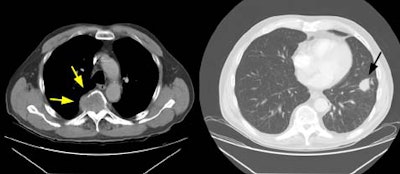

The patient below had an adenocarcinoma in the left lung that was obstructing the left upper lobe bronchus (left image upper row). The staging CT scan demonstrated a large liver cyst (*) and some underlying hepatic heterogeneity best appreciated on liver windows (yellow arrows). The patient had slightly elevated liver function tests, and the findings were felt to be most likely related to areas of sparing in a patient with some hepatic fatty infiltration. Because the possibility of metastatic disease could not be excluded, an MRI of the liver was performed. The heavily T2-weighed image shown (right image bottom row) revealed multiple liver metastases, many of which were not apparent on the contrast-enhanced CT scan (white arrows). MR imaging has been shown to be more sensitive for detecting liver metastases when compared to CT.